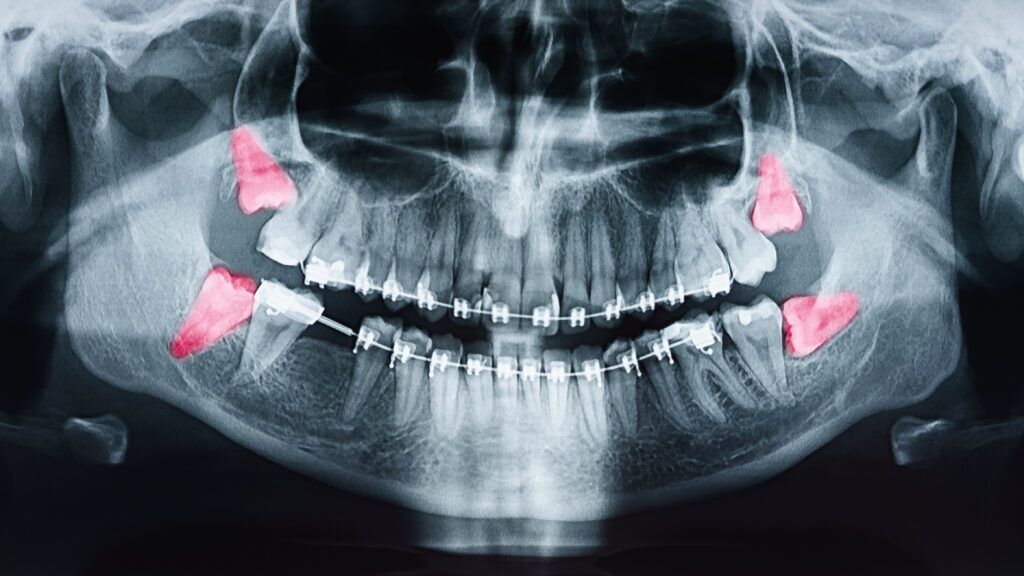

1. Initial Examination: During the first consultation, the dentist will examine the status of the wisdom teeth using X-rays or CT scans. The alignment, position, and available space for the teeth to emerge will be assessed to determine if extraction is necessary.

• Wisdom teeth are often unable to fully come out due to the lack of space, known as being impacted, which can lead to pain, swelling, and infection.

• Impacted wisdom teeth often result in tooth decay and gum disease due to difficulty in cleaning around them.

• Wisdom teeth can affect the alignment of other teeth by pushing against them.

• Cysts or tumors can sometimes develop around impacted wisdom teeth, potentially damaging the jawbone and other teeth if not addressed.